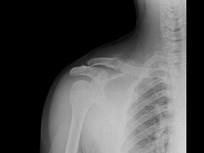

问题 男,18岁,右锁骨轻微疼痛,伴局部肿胀,结合图像,最可能的诊断是?(?)

选项 A.右锁骨正常 B.右锁骨嗜酸性肉芽肿 C.右锁骨骨囊肿 D.右锁骨骨结核 E.右锁骨骨巨细胞瘤

答案 B